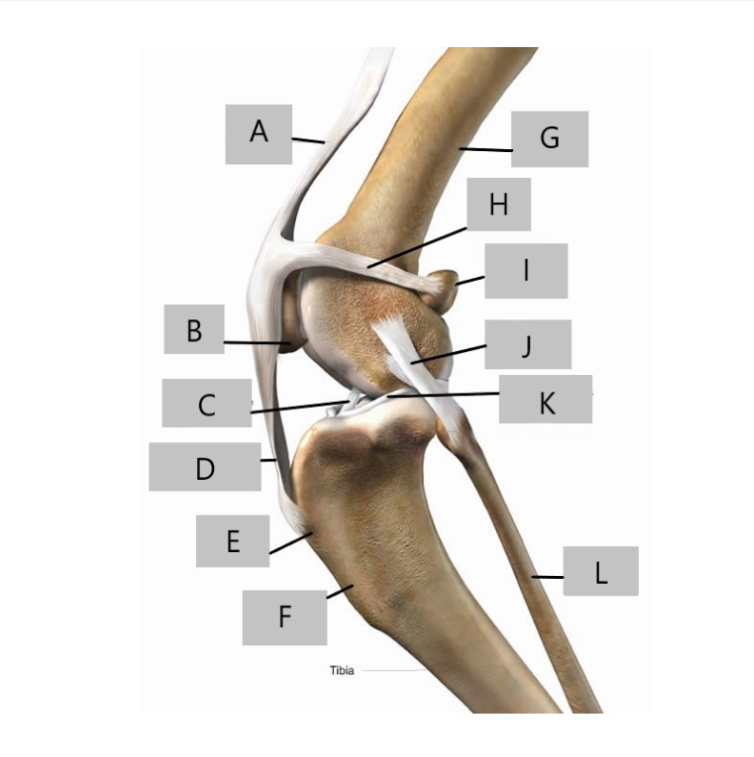

A

Quadriceps Tendon

B

Patella

C

Cranial Cruciate ligament

D

Patellar Ligament

E

Tibial Tuberosity

F

Tibial Crest

G

Femur Bone

H

Lateral Patellar Ligament

I

Sesamoid Bone

J

Lateral collateral Ligament

K

Meniscus

L

Fibula Bone